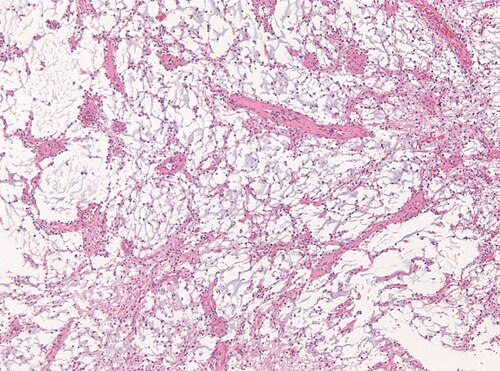

14 year old child with cognitive disturbances and hydrocephalus.

Left thalamus.

Low magnification. H&E stain.

PILOMYXOID ASTROCYTOMA GRADE II WHO WITH KIAA1549(Exon15)-BRAF(Exon9) FUSION

Comment: Pilomyxoid astrocytomas are a variant of pilocytic astrocytoma and share the same genetic abberations such as KIAA1549-BRAF fusions as seen in the current case. They usually lack the typical compact areas with rosenthal fibers seen in pilocytic astrocytomas. The tumors have been designated as WHO grade II tumours in the 2007 WHO classification, because of their tendency to recur more often.[1] A hypothalamic/chiasmatic location itself is a adverse prognostic factor.[2]